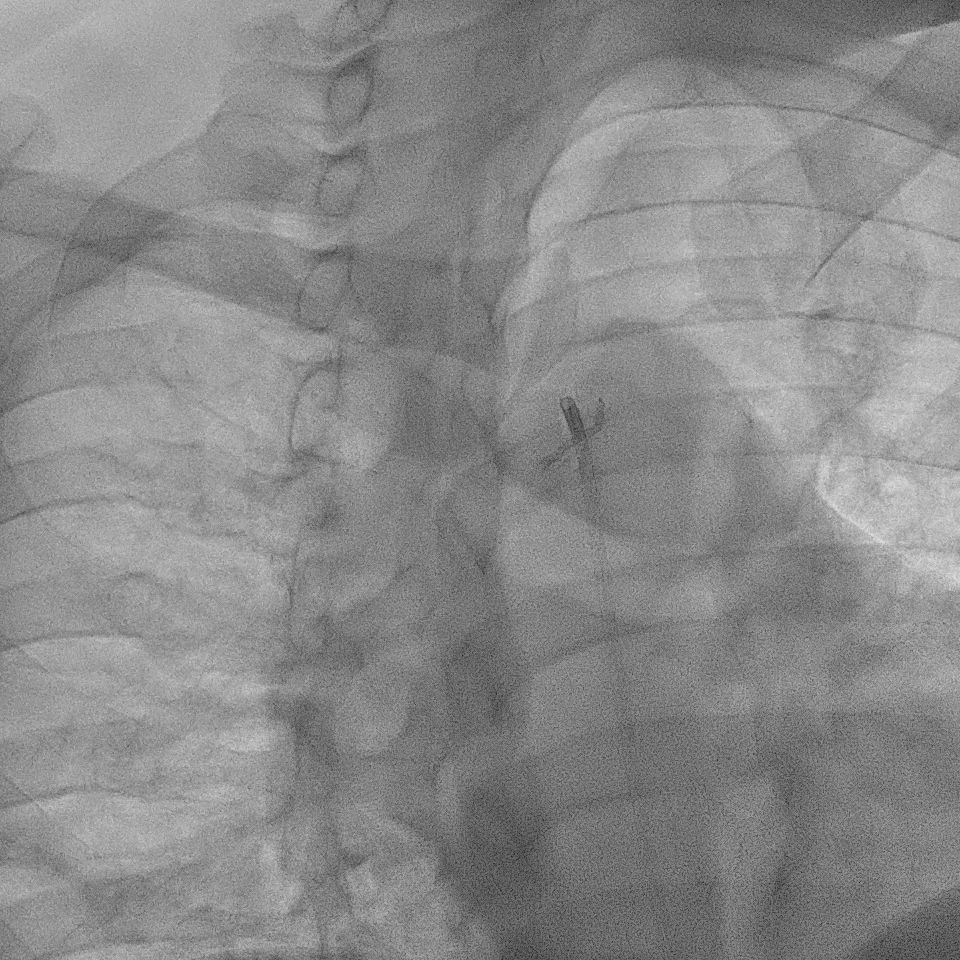

A right radial artery approach with 6Fr sheath was used. The right coronary system was engaged with 6Fr Judkin Right (JR4) guiding catheter. The posterior left ventricular branch was wired with Runthrough NS. Intravascular ultrasound (IVUS) showed distal RCA landing zone vessel size of 4.0-4.5mm in diameter. The mid RCA showed minimal luminal area (MLA) of 1.95mm2 with fibrous plaque and calcification at 12 o'clock. The proximal RCA landing vessel size was 4.5-5.0mm in diameter. The lesion was predilated with NC Trek Neo balloon 3.0x15mm. Attempted multiple times to deliver the stent SYNERGY 4.0X48mm but failed. The stent could not be passed into proximal RCA and eventually the distal stent edge crimpled and unable to be withdrawn into the guiding catheter. Tried to pull back system enbloc into the radial artery. Attempted to pull the stent into guider but failed again. The guiding catheter was removed. The stent was left with coronary wire in situ. Exchanged 6Fr radial sheath to slender sheath and attempted to snare stent with 2.0mm snare but failed. Attempted multiple wire wrapping technique with 3 BMW wires but failed. Decided to puncture right femoral artery with 8Fr sheath. A 7Fr JR4 guiding catheter was introduced into right brachial artery. A 7mm snare then snared the stent and removed it via femoral. The lesion was predilated with Scoreflex 3.5x20mm, stented with Supraflex Cruz 4.0x48mm and post-dilated with NC balloon 4.5mm. Result was TIMI 3 and no dissection.